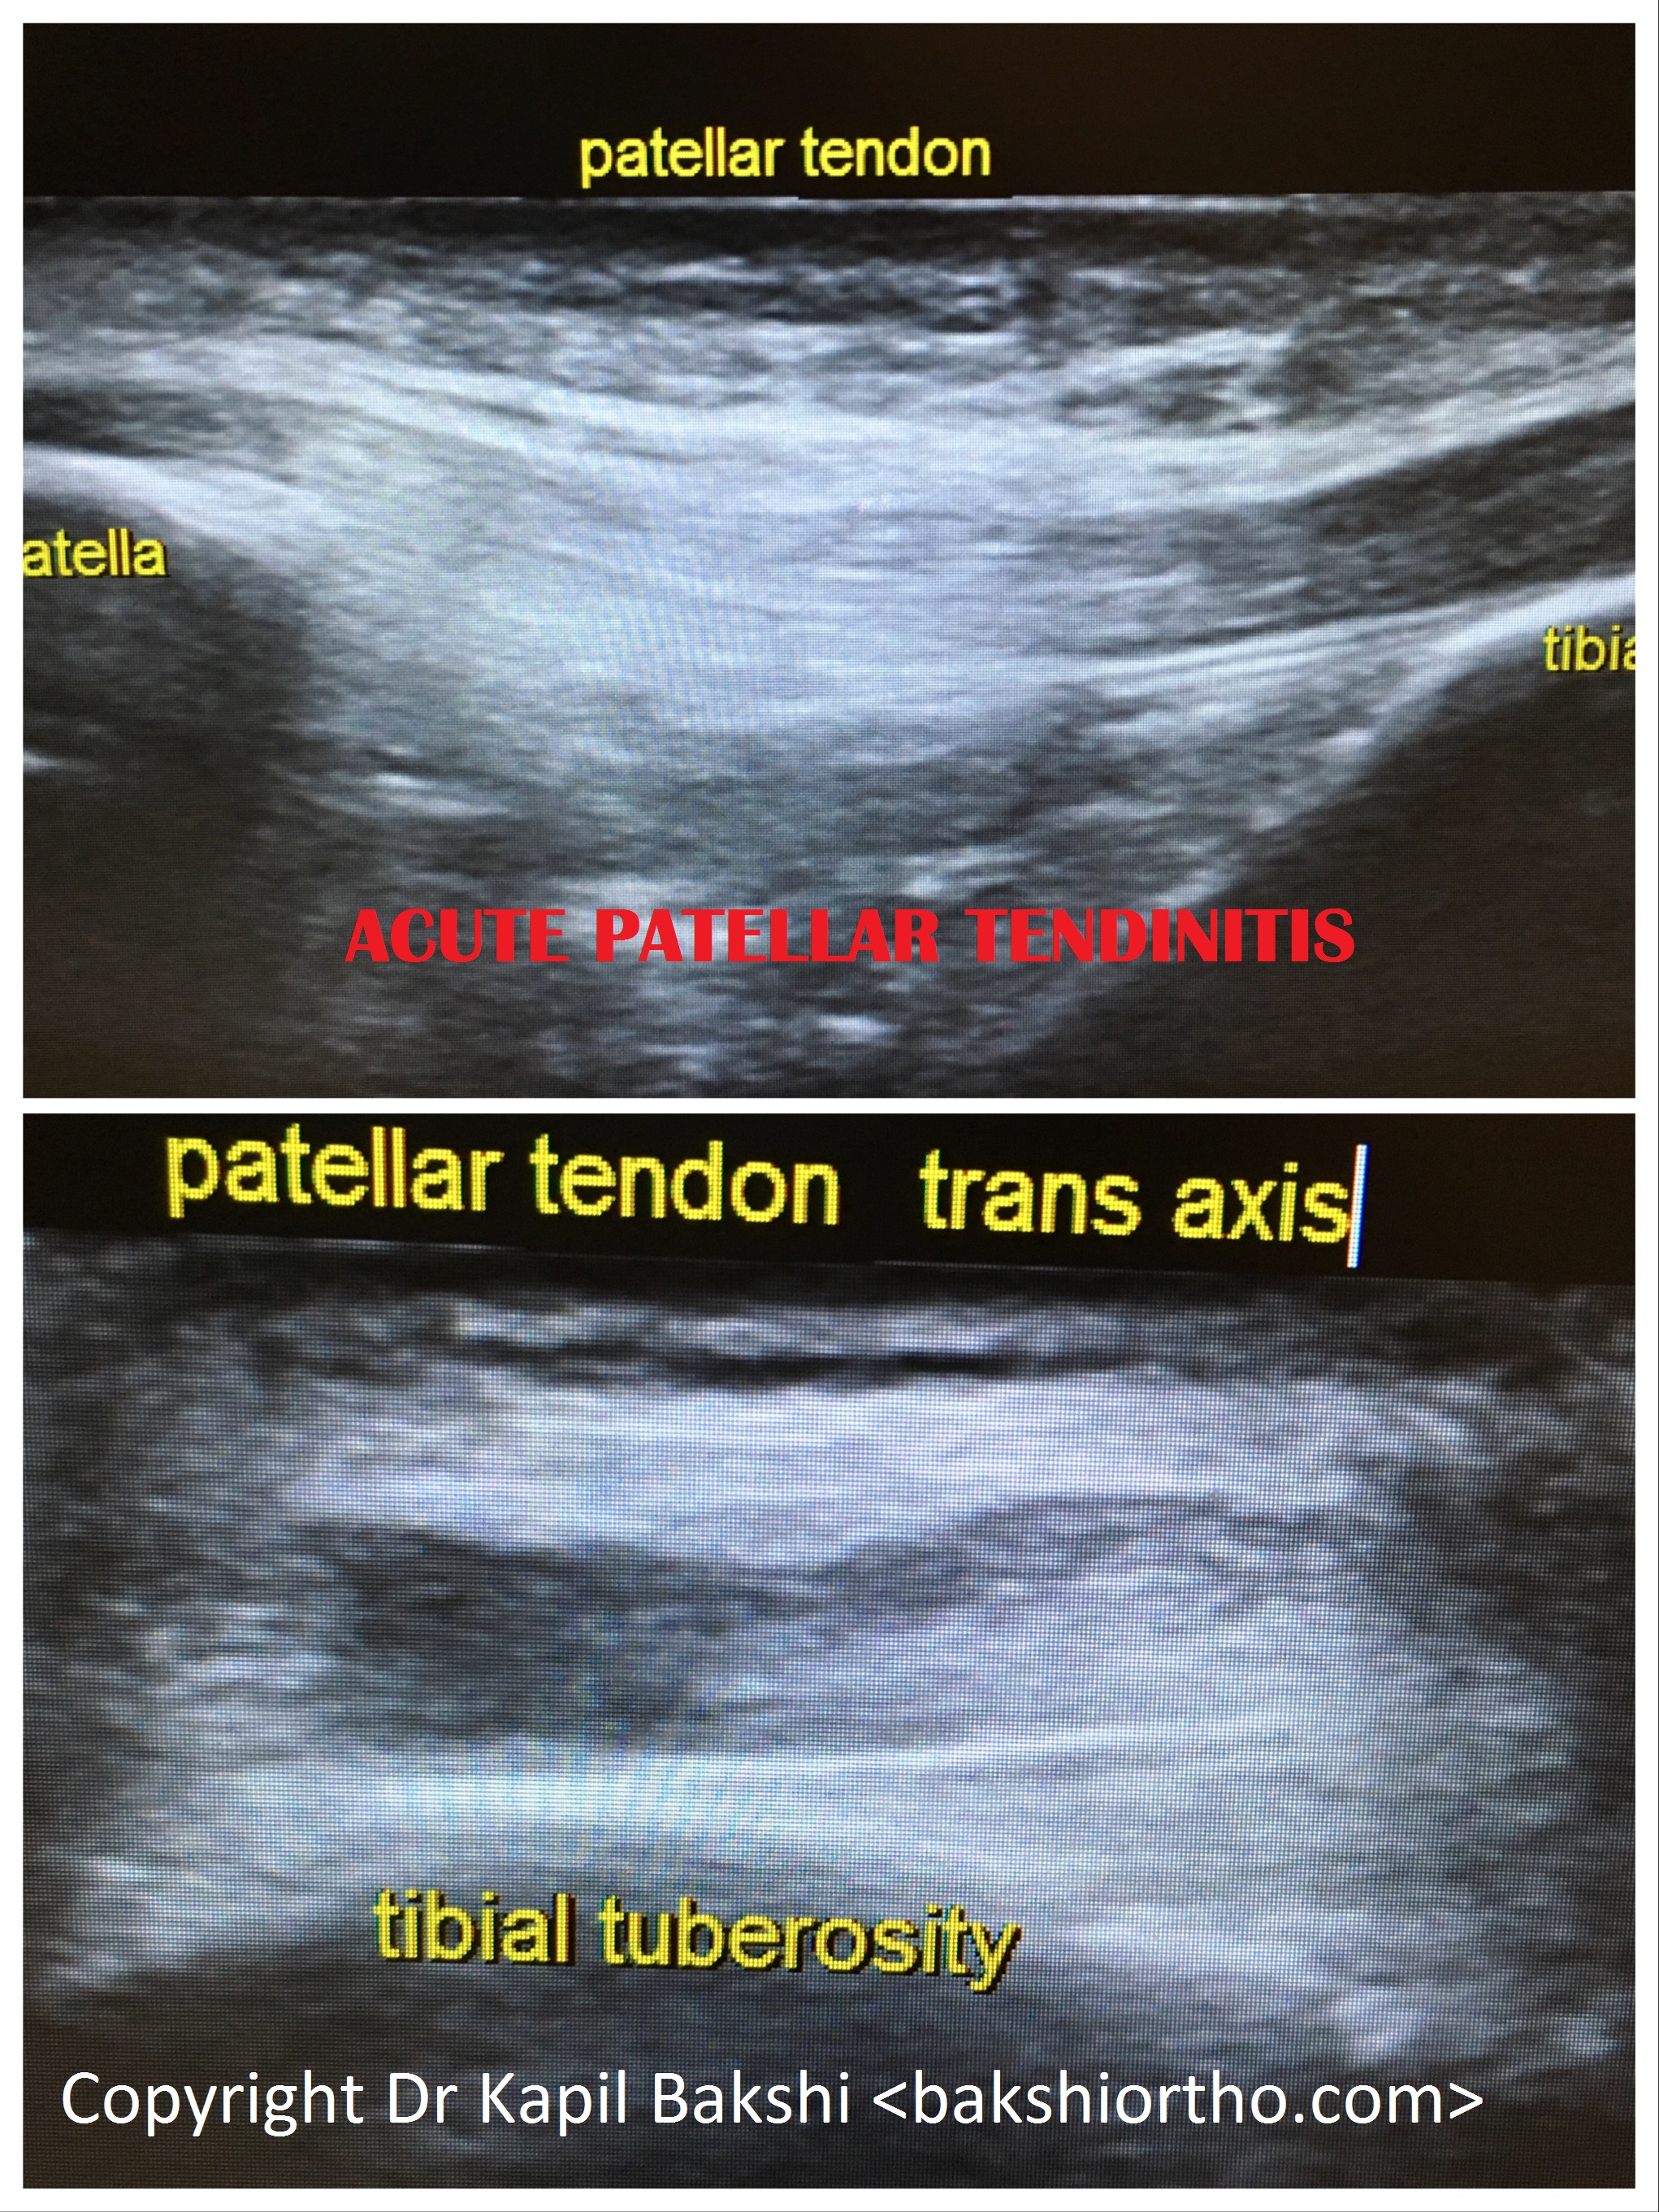

Orthopaedic Surgery: Sports Medicine: Prolotherapy: Trauma: Rehabilitation: Arthroscopy: Spine: MSK Ultrasound